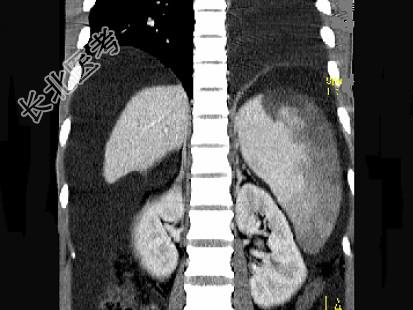

- 单项选择题患者男,29岁, 乙肝病史10余年,腹胀, 有移动性浊音,影像检查如图, 最全面的诊断是 ( )

A、肝硬化

B、肝硬化腹水

C、肝硬化腹水、脾梗、胆囊结石

D、大网膜膈下间位及脾梗

E、胆结石及脾梗